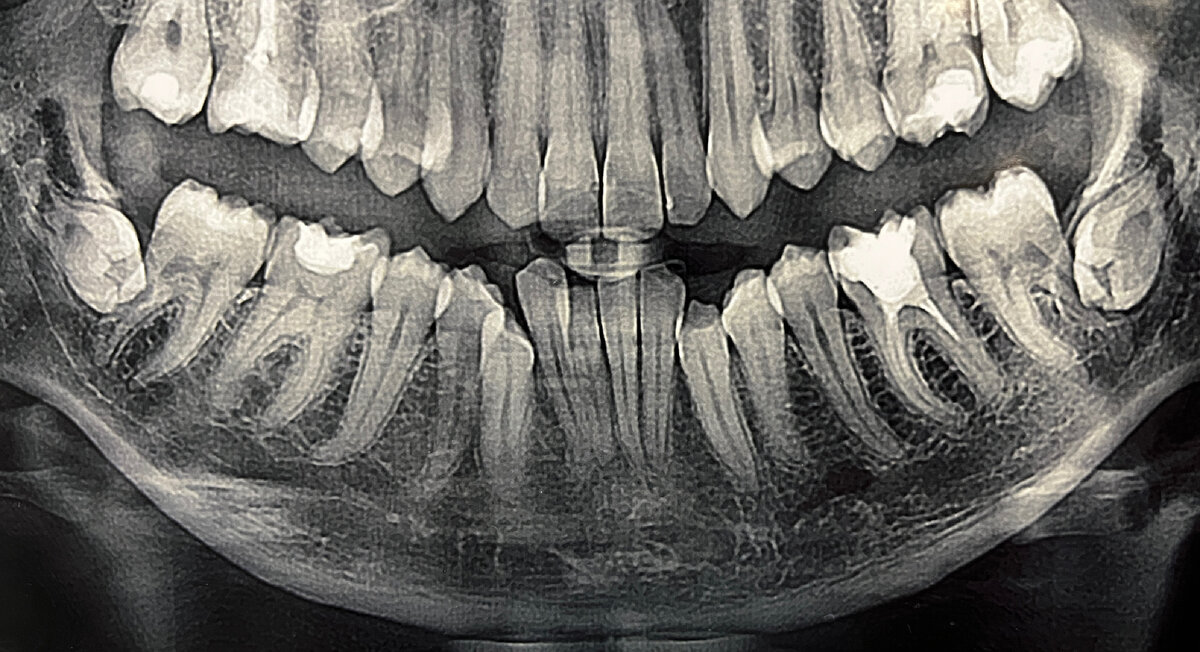

Моя история началась с того, что вдруг меня резко переклинило и я решила поставить себе брекеты. Со стороны так могло бы показаться, но на самом деле доолгие годы я планировала и мечтала о красивой здоровой улыбке. Постоянно мне что-то мешало: не хватка денег, времени и тд. Находилось милион причин, чтобы их не ставить. И в 2023 году я наконец-то решилась на эти изменения👍 Муж поддержал(огромное ему спасибо за это) и я начала действовать. Рассказала родственникам, они особо не были рады этому, говорили зачем тебе это нужно в 26 лет. Прожила столько лет и ничего, дальше так же проживешь. Я их конечно слушала, но моя цель превосходила все слова, которые мне говорили изо дня в день мои близкие😉Я настолько сильно хотела здоровую улыбку, что меня не останавливала даже та мысль, что перед установкой брекет-системы предстоит удалить два ретинированных зуба мудрости🦷 К моему удивлению, все прошло гладко. Я ожидала сильную невыносимую боль, в моей голове крутилось множество разных мыслей:

К моему удивлению, все прошло гладко. Я ожидала сильную невыносимую боль, в моей голове крутилось множество разных мыслей: " Вдруг врач не достаточно квалифицированный..Вдруг он заденет при удалении лицевой нерв и лицо перекосит..А вдруг..А вдруг". Но слава богу мне очень повезло с хирургом, прекрасный молодой доктор, знающий свое дело. Про таких людей говорят: "Поцелован Богом". Удалил мне два зуба безболезненно всего за 1 час. Здорово, когда все мои страхи превратились в пыль👍